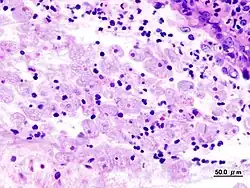

Biopsie du colon dans la dysenterie amibienne

La rectoscopie montre une muqueuse inflammatoire et hémorragique avec des ulcérations « en coup d'ongle ». La biopsie colique peut montrer en phase aigüe les microabcès « en bouton de chemise », et en cas d'amœbome, un granulome inflammatoire.